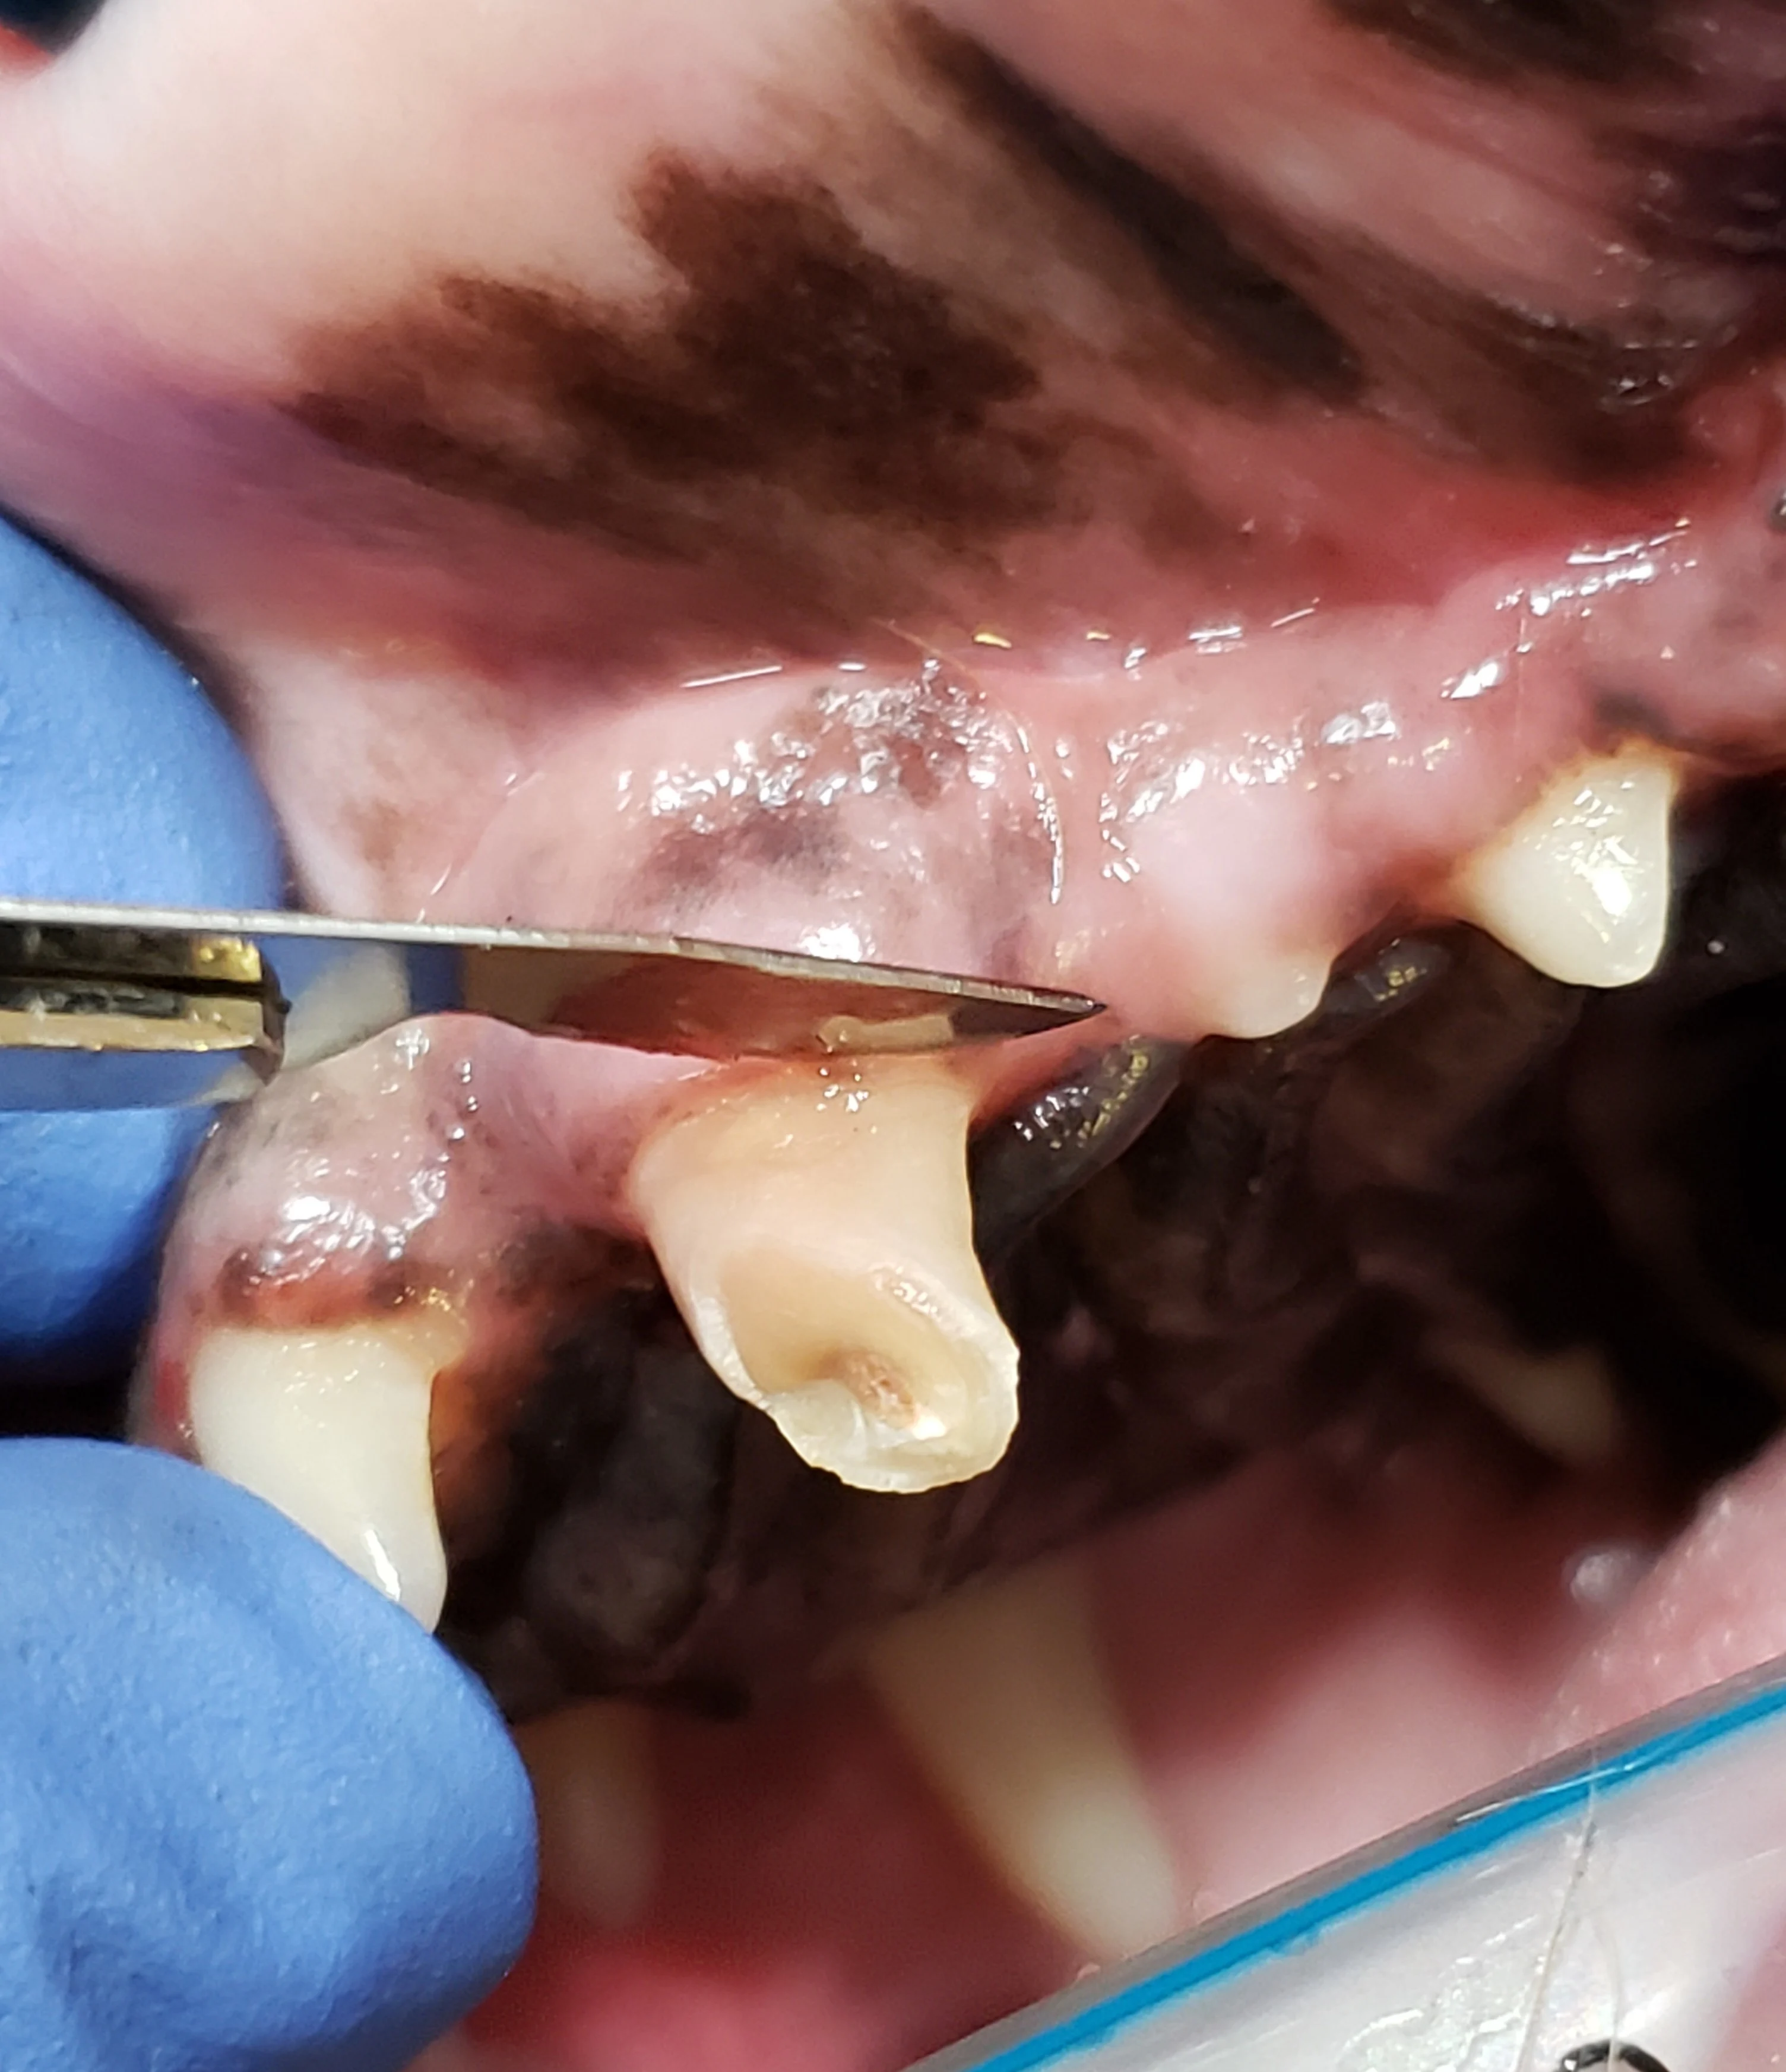

Step 1: Create a Fresh Edge

Incise 1 mm of tissue from the free gingival margin to create a fresh edge.

Author Insight

This step can also be performed by freshening the edge of the gingival flap directly prior to closure; however, in the author’s experience, creating a fresh edge at the beginning of the procedure can be simpler.